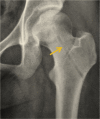

Steroid-associated osteonecrosis (SAON) is a common orthopaedic problem caused by administration of corticosteroids prescribed for many nonorthopaedic medical conditions. We summarised different pathophysiologies of SAON which have adverse effects on multiple systems such as bone marrow stem cells (BMSCs) pool, bone matrix, cell apoptosis, lipid metabolism, and angiogenesis. Different animal models were introduced to mimic the pathophysiology of SAON and for testing the efficacy of both prevention and treatment effects of various chemical drugs, biological, and physical therapies. According to the classification of SAON, several prevention and treatment methods are applied at the different stages of SAON. For the current period, Chinese herbs may also have the potential to prevent the occurrence of SAON. In the future, genetic analysis might also be helpful to effectively predict the development of ON and provide information for personalised prevention and treatment of patients with SAON.